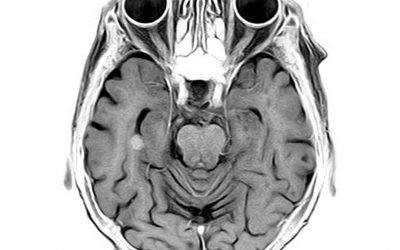

Harvey Cushing

Harvey Cushing (1869-1939) is considered to be the father of modern neurosurgery. His host of achievements ranged from pioneering important surgical techniques, introducing non-invasive sphygmanometry, to being the first person to describe Cushings disease. What is...